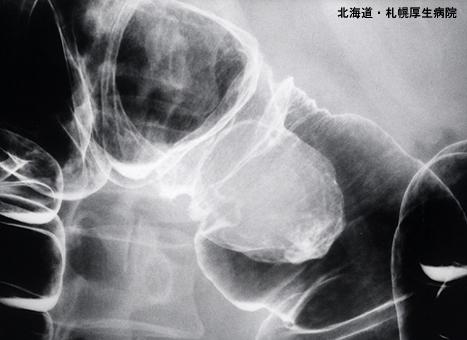

表现为亚有蒂性粘膜下癌形态的横结肠部位神经鞘瘤

Hokkaido Pref., 札幌厚生病院 (Dr. 今村)

良性非上皮性肿瘤/神经系统肿瘤

大肠/横结肠

X线

1型(肿瘤型)/

35~40

mp